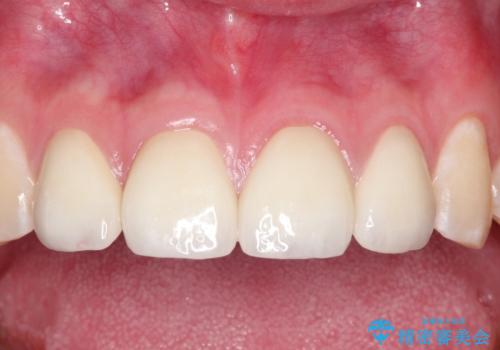

ご自身の歯を削る必要がありましたが、セラミッククラウンを装着することで、審美的改善ができました。